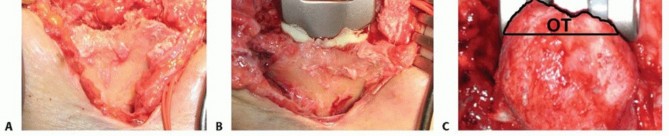

TECH FIG 6 •(continued)C,D. The triceps footprint to which reattachment should be attempted is predominantly on the flat part of the ulna or olecranon process, and not the tip, which is resected to prevent posterior abutment. E. Drill holes (1.5 to 2 mm) are oriented in a crossing fashion to secure the triceps to the footprint area. F. A separate cinch suture is used to increase the security and the area of contact between the triceps and the ulna, thereby improving healing potential.